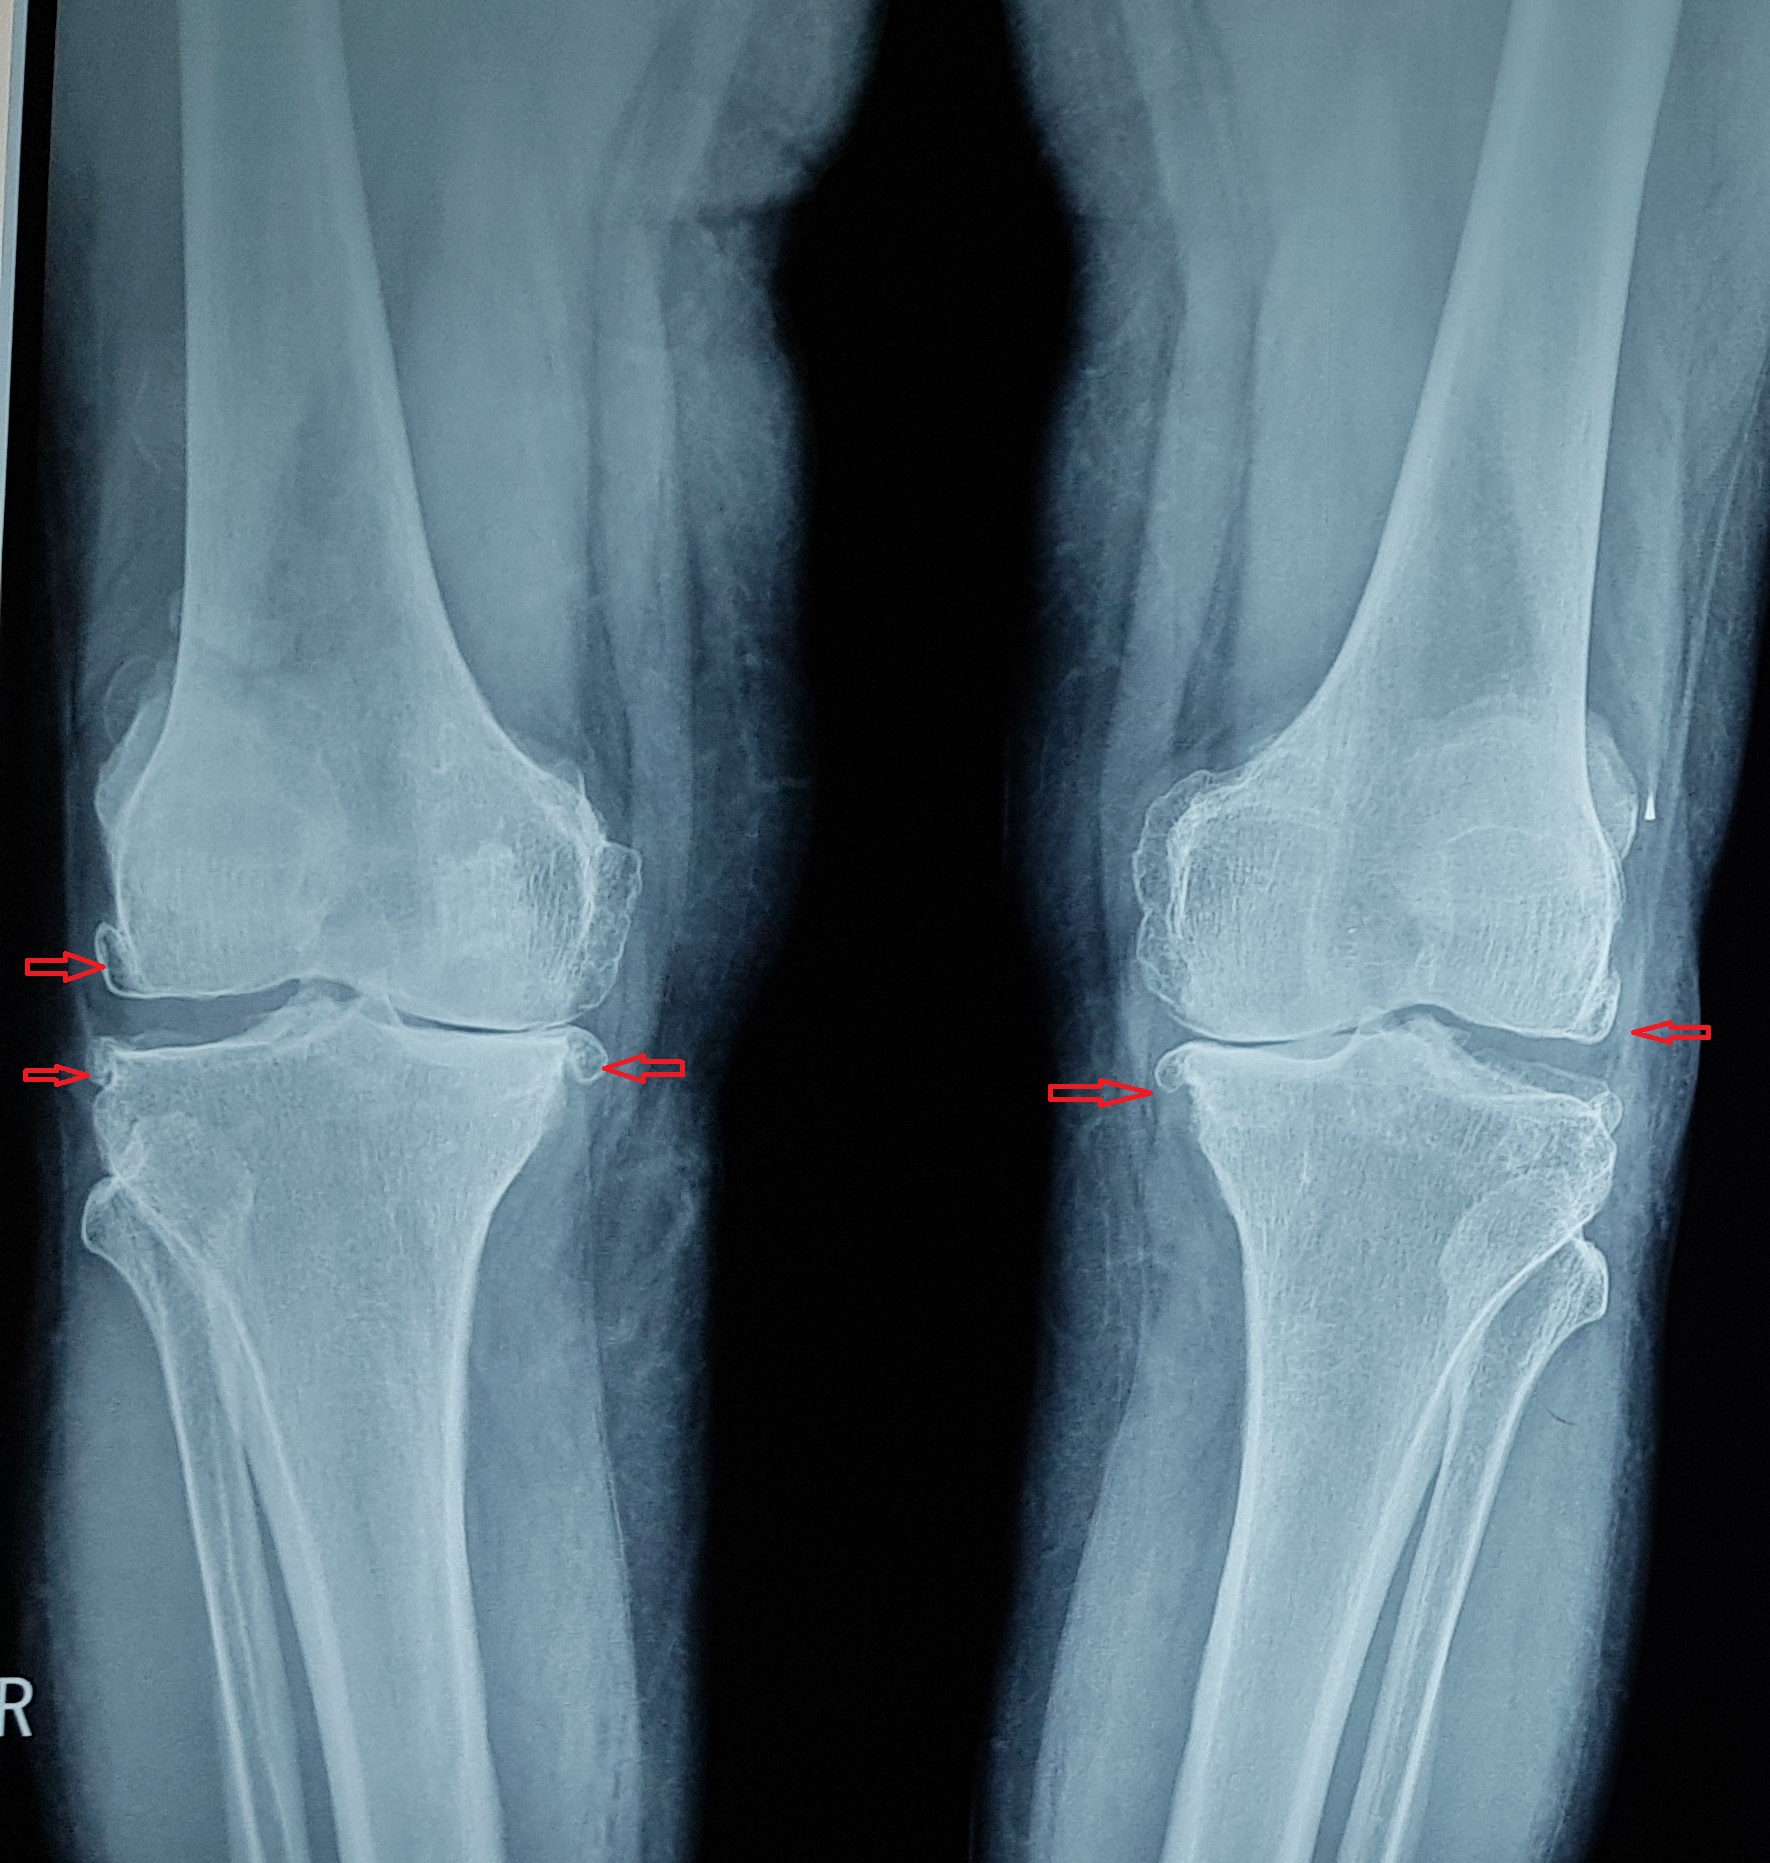

Немного вспомним. Остеоартроз — это дегенеративно-дистро-фическое заболевание суставов, характеризующееся первичной дегенерацией суставного хряща с последующими изменениями суставных поверхностей и развитием краевых остеофитов, что приводит к деформации суставов. «Остеоартрит» — синоним терминов «артроз» и «остеоартроз». А -ит на конце слова подчеркивает, что остеоартроз — это не только дегенерация сустава, но и воспаление, артрит (синовит), в суставе появляется патологическая жидкость («сары су»). Артроз коленного сустава (наиболее распространенный) называется гонартроз, тазобедренного — коксартроз. Если поражено много суставов, в том числе кисти — это полиостеоартроз («поли» — много). В народе эту болезнь называют отложение солей, хотя в суставе откладываются не просто соли, которые можно смыть, это твердые костные разрастания, остеофиты. Они бывают незначительные (в коленном суставе это 1-2 мм), средние — 4-5 мм и большие (свыше сантиметра). Остеофиты никуда не могут деться в результате терапевтического лечения, большие остеофиты чаще всего нужно оперировать. Об оперативном лечении — чуть позже.

большие остеофиты (стрелочки), неравномерное сужение

суставной щели (медиальное, ближе к центру).